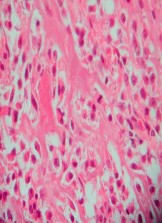

A 15-year-old male presents with deep knee pain awakening him at night. Radiographs show a permeative destructive lesion in the distal femoral metaphysis with a 'sunburst' periosteal reaction and Codman's triangle.

Biopsy confirms high-grade conventional osteosarcoma. What is the most critical prognostic factor for long-term overall survival in this patient?

Explanation

For localized high-grade osteosarcoma, the most important prognostic indicator is the histologic response to neoadjuvant chemotherapy. This is evaluated during the definitive resection. A 'good response' is typically defined as greater than 90% or 99% tumor necrosis. Patients who achieve this level of necrosis have a significantly improved disease-free and overall survival rate compared to 'poor responders' who have extensive viable tumor cells remaining.